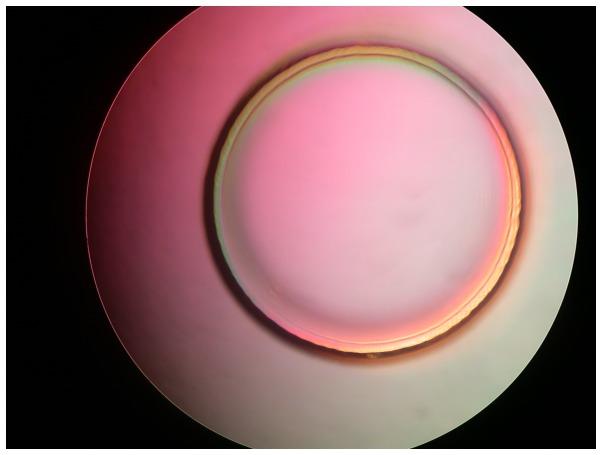

Because of the limitations of existing methods and techniques for directly obtaining real-time blood data, no accurate microflow in vivo real-time analysis method exists. To establish a novel technical platform for real-time in vivo detection and to analyze average blood pressure and other blood flow parameters, a small, accurate, flexible, and nontoxic Fabry-Perot fiber sensor was designed. The carotid sheath was implanted through intubation of the rabbit carotid artery (n = 8), and the blood pressure and other detection data were determined directly through the veins. The fiber detection results were compared with test results obtained using color Doppler ultrasound and a physiological pressure sensor recorder. Pairwise comparisons among the blood pressure results obtained using the three methods indicated that real-time blood pressure information obtained through the fiber sensor technique exhibited better correlation than the data obtained with the other techniques. The highest correlation (correlation coefficient of 0.86) was obtained between the fiber sensor and pressure sensor. The blood pressure values were positively related to the total cholesterol level, low-density lipoprotein level, number of red blood cells, and hemoglobin level, with correlation coefficients of 0.033, 0.129, 0.358, and 0.373, respectively. The blood pressure values had no obvious relationship with the number of white blood cells and high-density lipoprotein and had a negative relationship with triglyceride levels, with a correlation coefficient of -0.031. The average ambulatory blood pressure measured by the fiber sensor exhibited a negative correlation with the quantity of blood platelets (correlation coefficient of -0.839, P<0.05). The novel fiber sensor can thus obtain in vivo blood pressure data accurately, stably, and in real time; the sensor can also determine the content and status of the blood flow to some extent. Therefore, the fiber sensor can obtain partially real-time vascular rheology information and may thus enable the early diagnosis of blood rheology disorders and diseases.